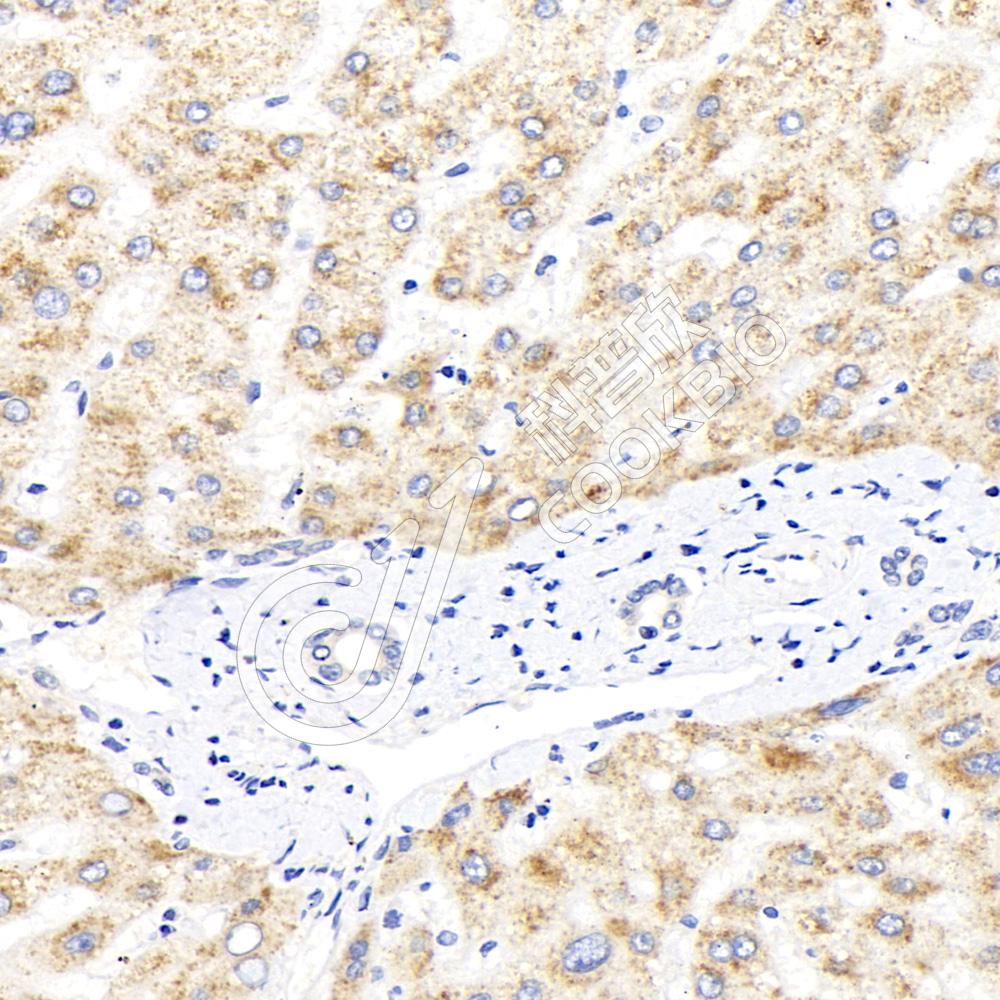

IHC检测AGXT蛋白(货号 K1340962).

样品: 人肝癌, 4%多聚甲醛 (货号KSG1101) 固定12-24小时.

抗原修复: 柠檬酸抗原修复液(干粉, pH 6.0) (KSG1201), 98℃, 20分钟.

—抗: 1: 1500稀释, 4℃ 孵育过夜.

二抗: S-vision免疫组化多聚二抗(山羊抗兔),即用型 (货号KB3906), 室温孵育20分钟.

样品: 人肝, 4%多聚甲醛 (货号KSG1101) 固定12-24小时.